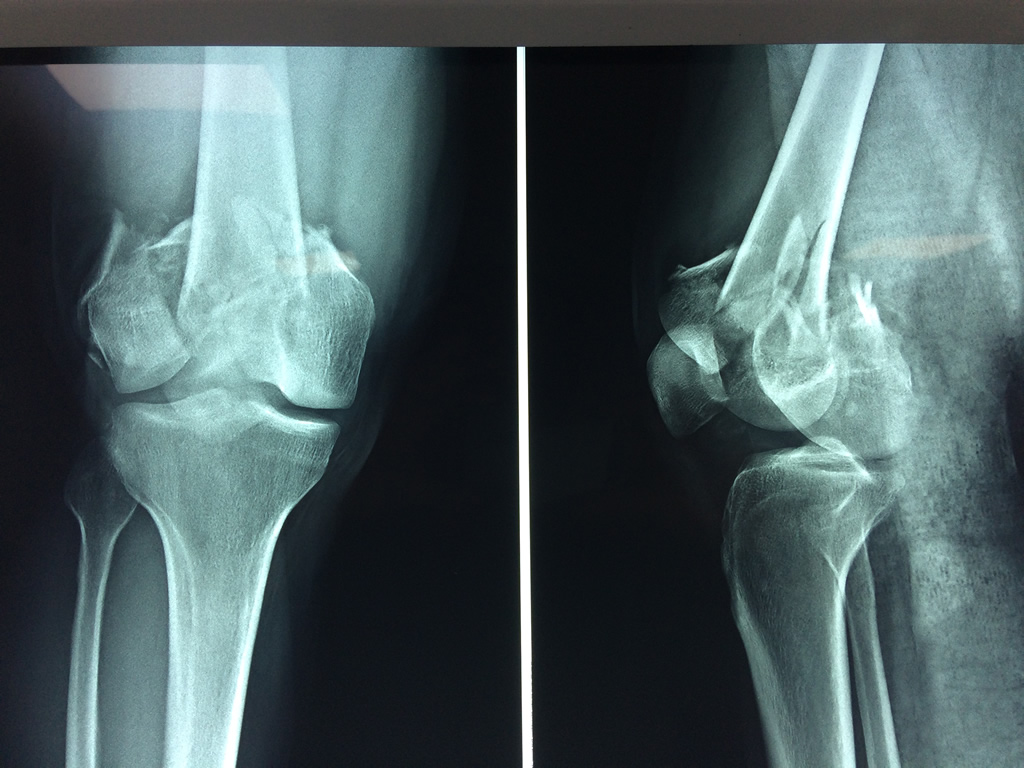

Cirugía de Tibia y Peroné